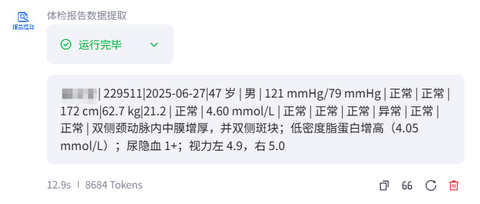

但在 2025 年,这座金字塔被一种看不见的酸液腐蚀了。这种腐蚀首先发生在企业的“连接处”。让我们看一个案例——一家物业公司的“驾驶员体检归档”流程。

在过去,这是一个典型的“中间层黑洞”。司机体检完把纸质报告扔给车队队长,队长把报告堆在桌上,月底再由行政专员一张张录入 Excel,最后由经理审核存档。这个过程涉及三个层级、四次信息转手,充满了延误和错漏。

但在 2025 年,这个流程消失了。或者说,它液化了。员工利用 AI 搭建了一套自动化系统,司机只需把体检单拍照上传,AI(OCR + 大模型)瞬间识别所有指标,自动归档,甚至能根据异常数据生成一份“有温度的健康建议”发回给司机。

整个过程不需要车队队长,不需要行政专员,不需要经理。这不仅仅是效率提升,这是组织架构的物理性毁灭。当 AI 可以零成本地完成“信息传递”和“初步决策”时,那些曾经依靠“上传下达”活着的中层管理者,突然发现自己站在了悬崖边。组织结构从金字塔变成了一个“飞碟”:中间极扁,只有一个发号施令的超级大脑,下面直接挂载着无数个自动运行的硅基引擎。